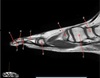

19

What is letter A?

20

What is letter B?

21

What is letter C?

22

What is letter D?

23

24

25

26

ACROMION

27

What is letter E?

SUPRASPINATUS TENDON

28

GREATER TUBEROSITY

29

What is letter G

SCAPULA